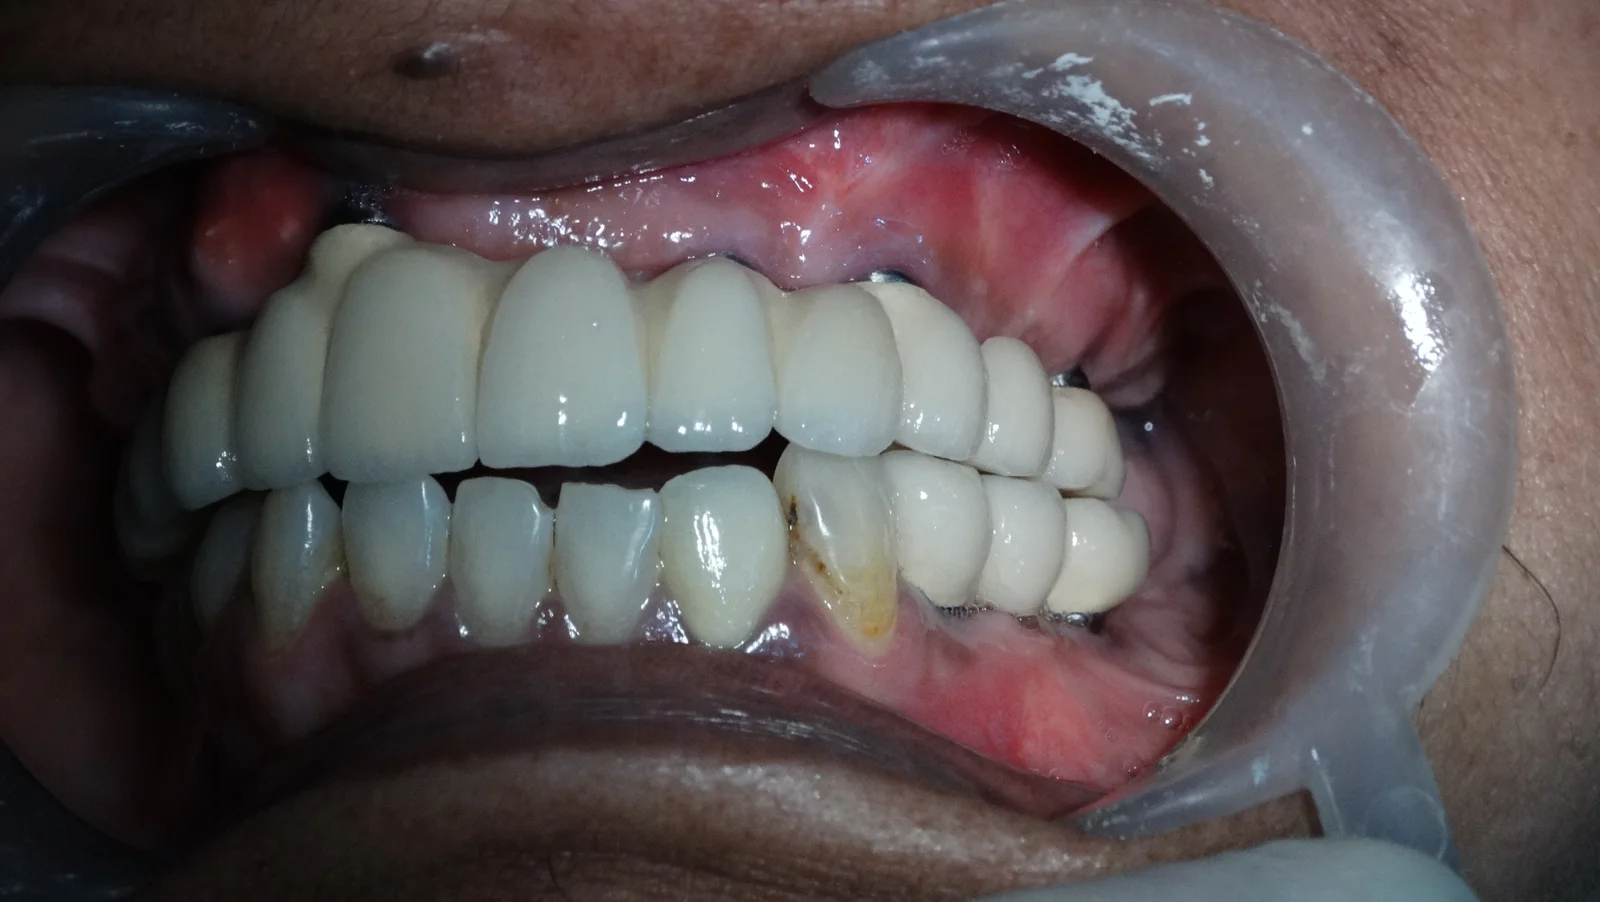

Full Mouth Rehabilitation

Implant Supported Fixed Teeth

Replacing all missing teeth with a permanent, fixed prosthesis that mimics the look, feel, and function of natural teeth. Explore our clinical transformations below.